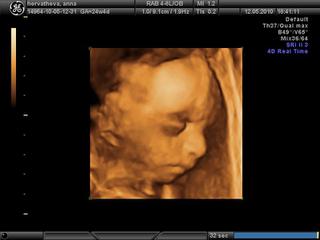

lucy1990 v 16-tom týždni keď ma hospitalizovali a robili mi sono a teraz dr. potvrdila že áno, bude to chlapček 🙂 ale už aj môj dr. skonštatoval že "z toho dievčatko neurobím ani keby som chcel" ... ale hlavne nech je zdravý a budeme ho strašne ľúbiť 😉 a podľa 3D sona prvého synčeka a teraz "ako cez kopirák" sa podobajú 😀

Zuzi, tiez som mala taky pocit, ked som bola prvy krat teraz v tom 26tt, absolutne nic nebolo vidiet v tej spleti pupocnej snury, noziciek a ruciciek, doktorka ma dobala do bruska tou sondou, ze som ju sama musela zastavit...potom nas preobjednala na dalsi krat a tam sme videli to co mam v albume, nikdy nie celu tvaricku, ale tak aspon mi urobila morfo organov, vsetky merania...ale tiez som od toho cakala viac 😒 nuz ale babatku nerozkazes, ako sa ma natocit 😅